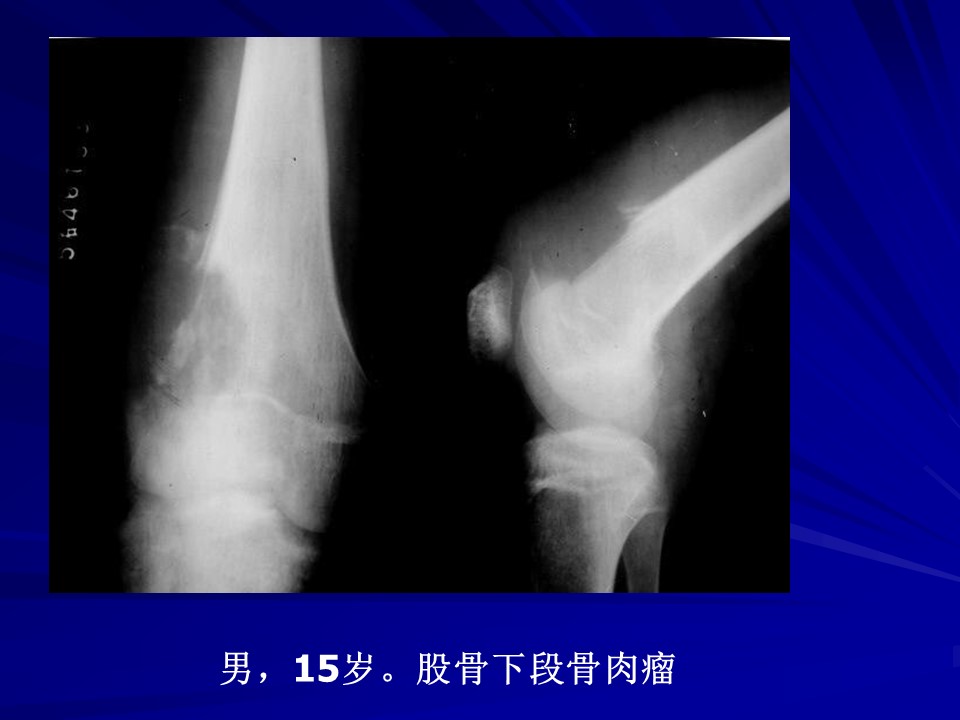

“常见骨肿瘤的X线诊断” 的相关文章